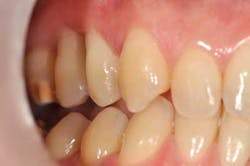

The occlusal equilibration has been performed in order to get the maxillary premolars out of the way during mandibular eccentric movement while maintaining intercuspation contacts on the palatal cusps. The patient immediately felt an improvement of her bite.

Fig. 5: The occlusal equilibration consisted in unloading tooth No. 4 during the lateral excursion of the lower jaw and now enables a canine guidance